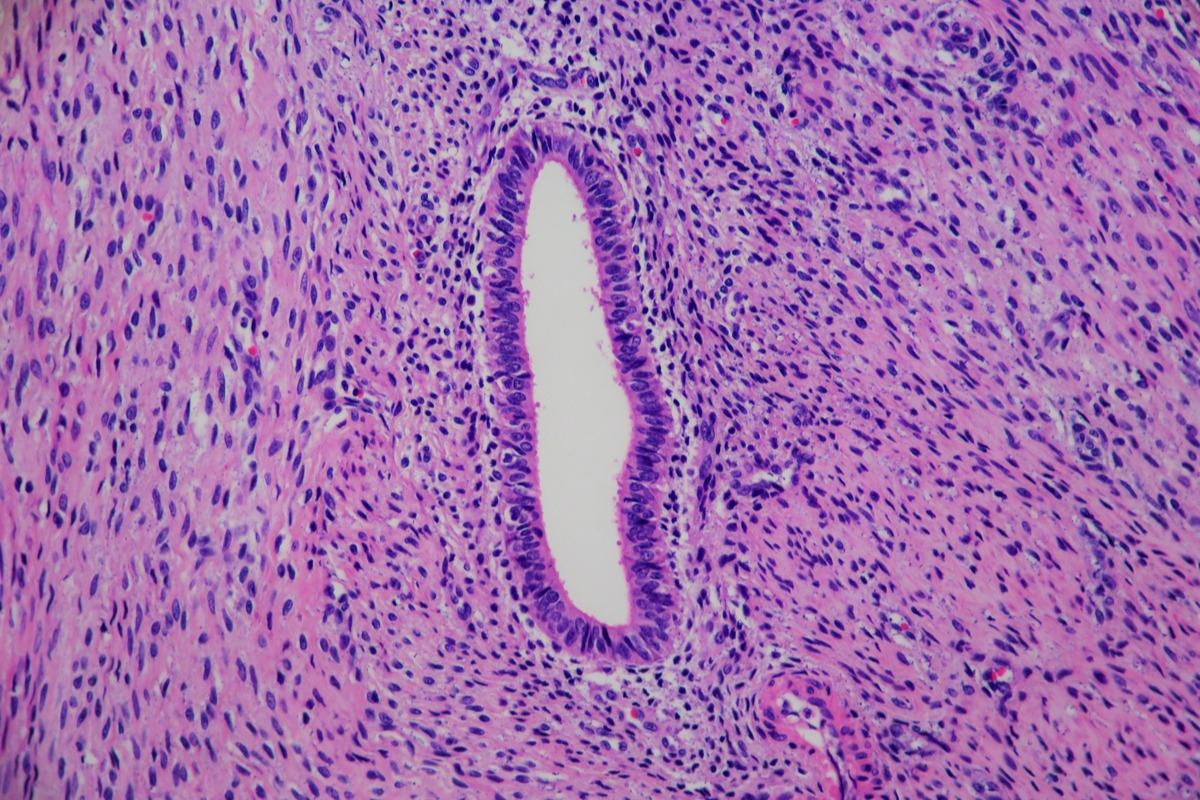

Adenomyosis is a condition that affects the uterus and is histologically characterized by ectopic endometrial glands and stroma located in the myometrial, which are surrounded by hypertrophic (a lodgement caused by the increase in the size of cells) and hyperplastic (enlargement caused by an increase in cell proliferation)  myometrial changes. The myometrium is the middle layer of the uterine wall, which is comprised of smooth muscle cells and controls the contraction of the uterus.

Adenomyosis of the uterus. Image Credit: Lisa Culton/Shutterstock